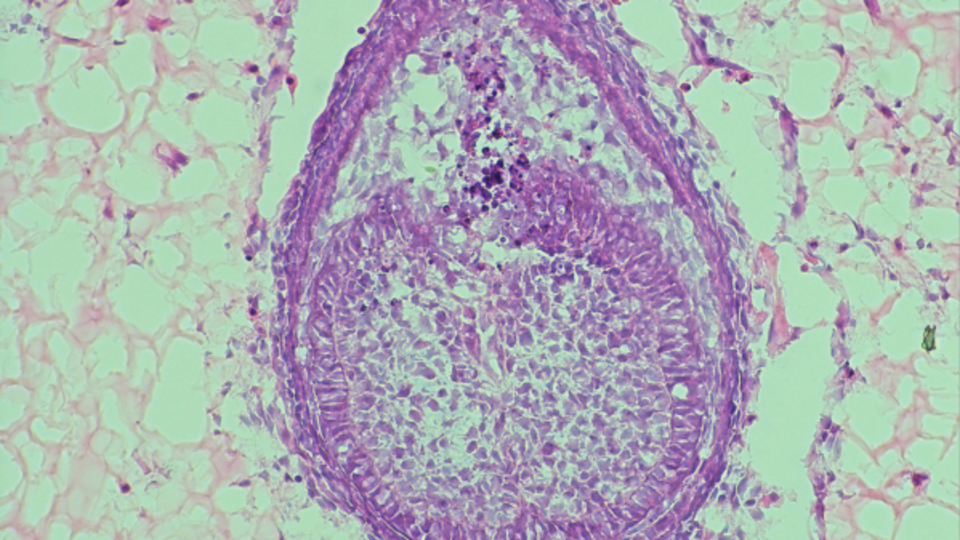

تعتبر البيئة، التي يطلق عليها الباحثون “السقالة”، ضرورية لتكوين الأسنان المزروعة في المختبر، وهي موضوع أحدث دراسة أجراها فولبوني. في عام 2013، استخدم فولبوني سقالة مصنوعة من بروتين الكولاجين، ولكنه يستخدم الآن هيدروجيل، وهو نوع من البوليمر يحتوي على نسبة عالية من الماء، كما أوضح شيويتشن تشانغ، طالب الدكتوراه في جامعة كينجز كوليدج في لندن، والمؤلف المشارك للدراسة. وقال: “نقوم بجمع الخلايا أولا من أجنة الفئران ثم نمزجها معا وندورها للحصول على كريات صغيرة من الخلايا”. “ثم نقوم بحقن هذه الكريات الخلوية داخل الهيدروجيل ونزرعها لمدة ثمانية أيام تقريبًا.” ولأن العمل يركز على البيئة، ليست هناك حاجة للخلايا البشرية.

وفي نهاية الأيام الثمانية، ستتشكل هياكل تشبه الأسنان داخل الهيدروجيل، والتي تم تطويرها بالتعاون مع إمبريال كوليدج لندن. في بحث عام 2013، تم نقل هذه “بدايات الأسنان” إلى فأر حيث تطورت إلى بنية أسنان كاملة مع تطوير الجذور والمينا.